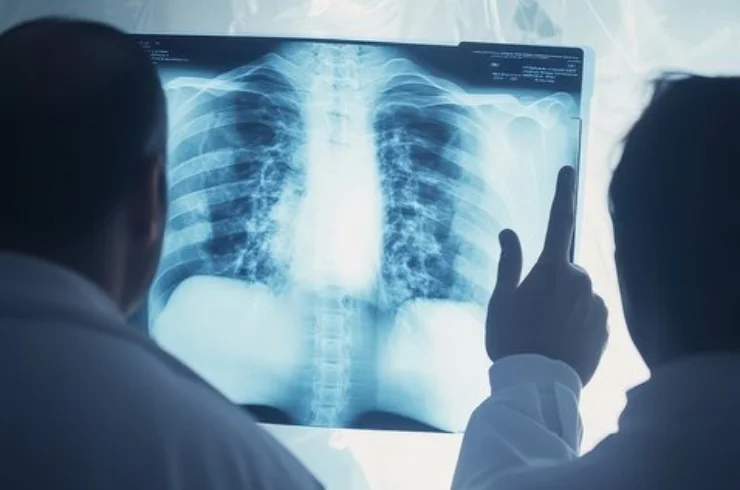

Diagnostic X-ray imaging for accurate assessment of bone and joint conditions, injuries, and more.